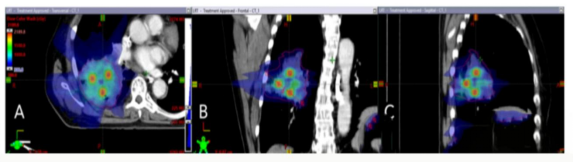

重离子治癌是先进有效的放疗方法,被国际上公认为21世纪最理想的肿瘤放射治疗技术,特别适宜用于外科手术、化疗、常规放疗无效或易复发的难治病例,适用于全身实体肿瘤的放射治疗。重离子射线进入人体后,在肿瘤部位形成“布拉格峰”,能量集中释放,对肿瘤细胞的DNA双链造成不可修复的断裂,从而杀死癌细胞。与传统放疗相比,重离子射线的生物学效应更强,对乏氧肿瘤细胞和传统放疗不敏感的肿瘤效果显著,并且具有对病灶周围健康组织损伤最小,对癌细胞杀伤效果好等优势,患者日常活动不受影响,疗程短、无痛苦,几乎没有副作用。

是一种新兴的精准放疗技术,通过三维网格化剂量分布,利用空间分割放疗技术,在肿瘤内部构建不均匀剂量分布。高剂量“晶格点”集中于肿瘤内部,形成“峰谷”结构,既能高效杀灭肿瘤细胞,又能通过低剂量区域保护正常组织。这种三维剂量分布突破了传统放疗的均匀照射模式,显著降低对周围器官的辐射损伤在肿瘤内部形成高剂量“晶格点”与低剂量区域交替的格局,实现对肿瘤细胞的精准杀伤,同时最大限度保护周围正常组织。